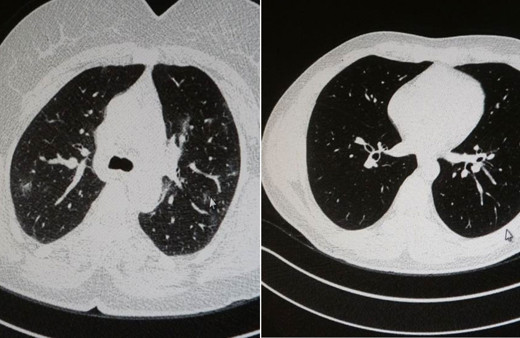

Akciğer